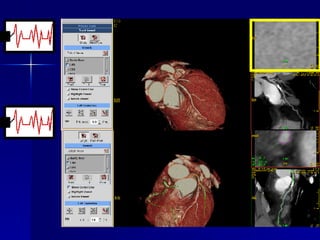

Torax CARDIACAS Angiografía coronaria no invasiva Caracterización de placa Anomalías congénitas Post operatorios (vascular y otros) Pre y post ablación  Perfusión miocárdica Análisis volumétrico Anatomía del ventrículo izquierdo Motilidad parietal Tumores cardíacos Morfología de las venas pulmonares

Torax CARDIACAS Indicaciones angiografía: Con factores de riesgo Pruebas funcionales dudosas Pruebas +, pero rechazan angio invasiva Con cirugía de revascularización  Con sospecha de puentes musculares Anomalías coronarias

Target Applications Coronary Arteries Stenosis Evaluation Coronary Bypass Graft Patency Volume rendering and Virtual Endoscopy of: Coronary Arteries Pulmonary arteries Bronchi Cardiac Motion analysis Cardiac Functional Analysis Cardiac Perfusion

Functional –  Ejection Fraction Diastole Volume = 163 cc Systole Volume = 77 cc Ejection Fraction   = 53%